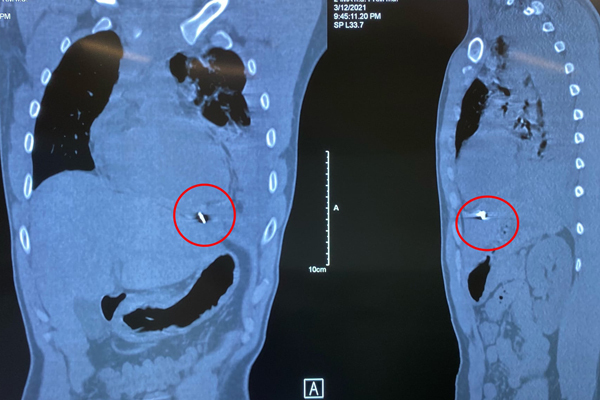

Hình ảnh mảnh kim loại găm trong tim bệnh nhân

Bệnh nhân được thở oxy, theo dõi sát tình trạng hô hấp, đồng thời khảo sát bằng siêu âm và chụp CT lồng ngực, phát hiện tràn máu màng phổi trái mức độ nhiều, kèm xẹp phổi trái, có mảnh kim khí nằm trong cơ hoành, mặt dưới tâm thất trái.

Các bác sĩ thực hiện mở ngực đường bên vào khoang màng phổi trái, lấy ra dị vật là mảnh kim loại dài 1cm và gần 1,5 lít máu, máu đông rồi khâu lại cơ tim cầm máu, dẫn lưu màng tim, màng phổi trái.

Dị vật có cạnh sắc nhọn làm rách mặt trước màng tim và găm vào mặt hoành của màng tim, gây chảy máu dữ dội, tràn vào khoang màng phổi trái.